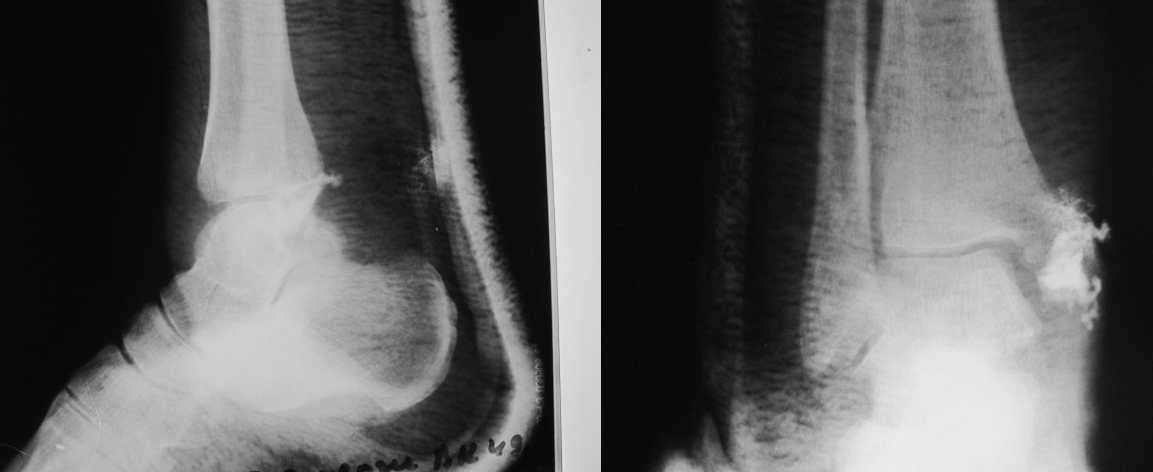

Уважаемые коллеги! Помогите определиться с тактикой лечения больной 50 лет! Травма в результате ДТП 1 января 2011г. открытый многооскольчатый перелом медиальной лодыжки левого голеностопного сустава со смещением. При поступлении в области медиальной лодыжки поперечная рана 5,0х1,0 см. сильно загрязнена, была выполнена ПХО. 05.01.2011г. сняты все швы по поводу нагноения раны, выполнена некрэктомия нежизнеспособных краев раны. На сегодня голеностопный сустав незначительно отечен, слегка болезнен при пальпации в области медиальной лодыжки. Температура тела нормальная, боли практически нет. Кровь спокойная. В области медиальной лодыжки имеется ранка округлой формы до 0,3 см., со скудным гнойным отделяемым (следы на салфетке после перевязки 1 раз в 2 дня). Посев из раны выполнить невозможно. На последних контрольных рентгенограммах признаки остеомиелита медиальной лодыжки? Помогите определиться с тактикой лечения: оперативное? Консервативное? С уважением Александр Белоконь!

4 недели после травмы - это еще пока открытый срастающийся инфицированный перелом, а не остеомиелит. Что касается рентгенограмм - в таком разрешении трудно оценить структуру кости.

Уважаемые коллеги! Прошу прощения за собственную невнимательность. У больной травма не 1 января 2011г., а 1 декабря 2010г., т.е. уже 2 месяца.

Прилагаю данные фистулогрфии. Основной вопрос, все же, лечить консервативно или оперативно? Если оперативно, то какой объем? А что если прийдеться резецировать всю медиальную лодыжку!?